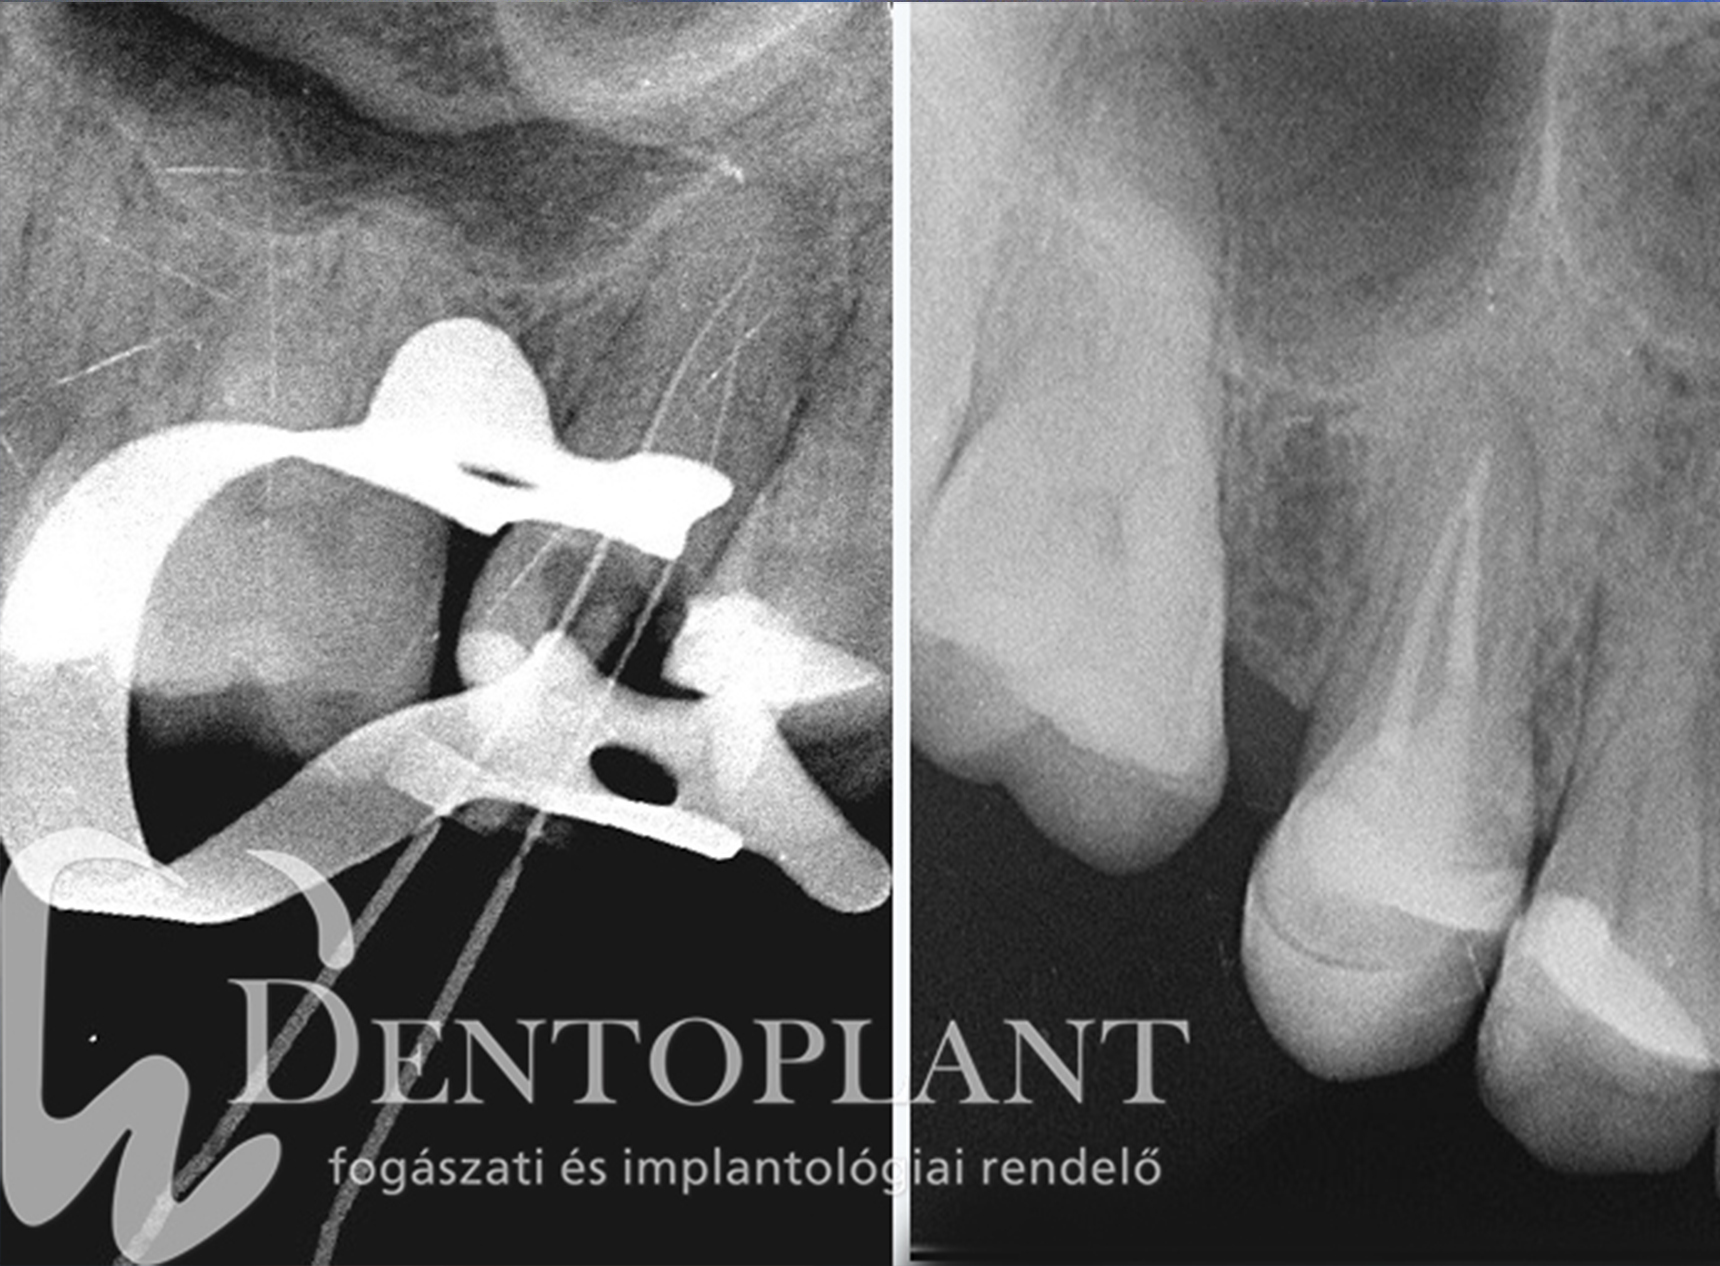

Betört eszköz eltávolítása mikroszkóp segítségével – Esetbemutatás

Mellékelt fotókon egy olyan esetet mutatunk be, amikor egy másik rendelőben betört eszköz eltávolításához kérték segítségünket. Ez egy klasszikus példa arra, milyen előnyökkel jár, ha egy jól felkészült specialista mikroszkóp mellett tud dolgozni..

A páciens egy korábban megkezdett gyökérkezeléssel érkezett. A kezelést eredetileg megkezdő orvosnak egy nagyon szűk csatornában betört az eszköze, így a csatorna tisztítása az akadály miatt nem lehetséges. A betört darab teljesen elzárta az útvonalat, így a gyulladás nem tudott megszűnni.

Önmagában a betört eszköz nem feltétlen jelent gondot, de ha alatta fertőzött fogszövet marad, az nem tisztítható ki, így ebben az esetben a fog csak akkor menthető meg, ha az adott betört tűt sikerül eltávolítani.

A megoldás mikroszkóp alatt születik, mert mikroszkóp nagyításának segítségével:

• pontosan be tudjuk határolni a betört tű helyét,

• speciális ultrahangos műszerekkel körbemozgatva

• eltávolításra került a csatornából.

Az eredmény = a fog megmentése

A fogat sikerült megmenteni, a gyulladás megszűnt, és a páciens teljesen panaszmentessé vált.

Az eset szépen mutatja, hogy mikroszkóp nélkül az eszköz eltávolítása jó eséllyel lehetetlen lett volna, és a fogat el kellett volna távolítani